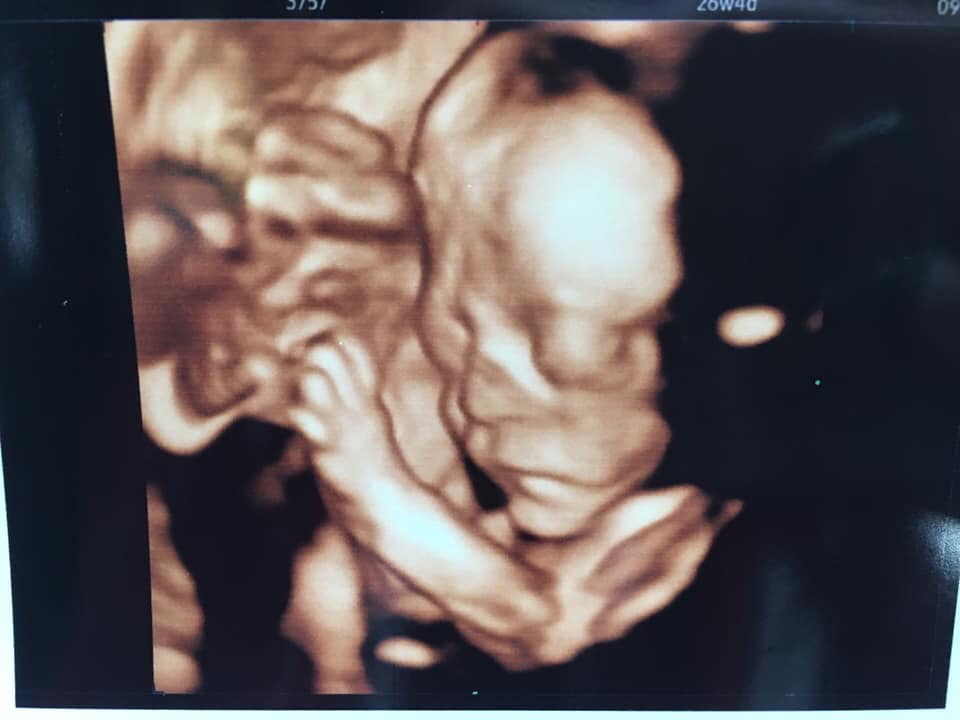

แค่นี้ถือว่าโด่งมั้ยค่ะ🥰